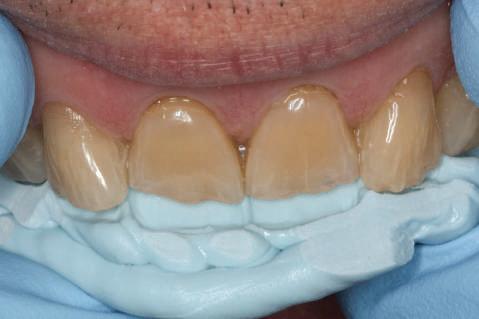

Cazul (2)

Repreparea intraorală a bonturilor cu amprente extraorale

Acest caz prezenta probleme de recesie similare cu cele menţionate anterior. Deşi bonturile au fost re-preparate intraoral pentru a urma noile margini tisulare, s-a decis amprentarea în afara cavităţii orale pentru a evita manipularea ţesutului pacientului cu biotip subţire. Fiecare bont individualizat s-a îndepărtat şi s-au inserat imediat bonturi de vindecare pentru a evita colapsul ţesuturilor.

Atitudine: Fiecare bont individualizat s-a aplicat pe câte un analog de implant. Fig. 6 prezintă bontul nou preparat pe analogul său cu inel de cupru de dimensiuni mari pentru a susţine

materialul de amprentare (alternativ, s-ar fi putut utiliza o lingură de amprentare universală pe cadran pentru a asigura suport pentru materialul de amprentare). Fig. 7 prezintă bontul individualizat cu ceară aplicată pentru a preveni pătrunderea materialului de amprentare în camera de acces a şurubului, iar fig. 8 ilustrează tehnica de amprentare care evită necesitatea plasării unui şnur de retracţie în şanţ în jurul implantului. Această tehnică este, de asemenea, utilă pentru adăugarea la marginile restaurării provizorii.

Cazul (2): Repreparea intraorală a bonturilor cu amprente extraorale

Figurile

6. Bontul nou preparat pe analog.

7. Bont individualizat cu vată şi ceară.

8. Tehnica de amprentare.